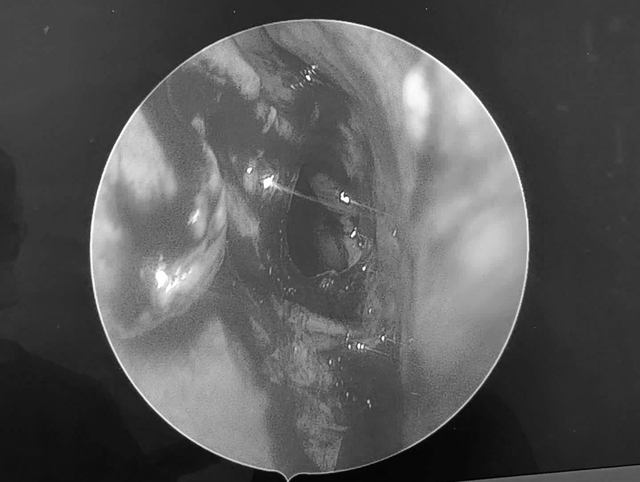

Kết quả chụp chụp MRI cho thấy cụ B.Ph có một khối u nhầy xoang bướm

ẢNH; C.X

Kết quả MRI cho thấy không ghi nhận xuất huyết, nhồi máu hay khối u não mà xác định bệnh nhân bị u nhầy xoang bướm gây lan vào đỉnh hốc mắt trái.

Ngay sau đó, bác sĩ Nguyễn Thanh Tiên cùng ê kíp đã tiến hành phẫu thuật mở xoang bướm và lấy sạch bệnh tích, dẫn lưu bằng phương pháp nội soi mũi xoang.